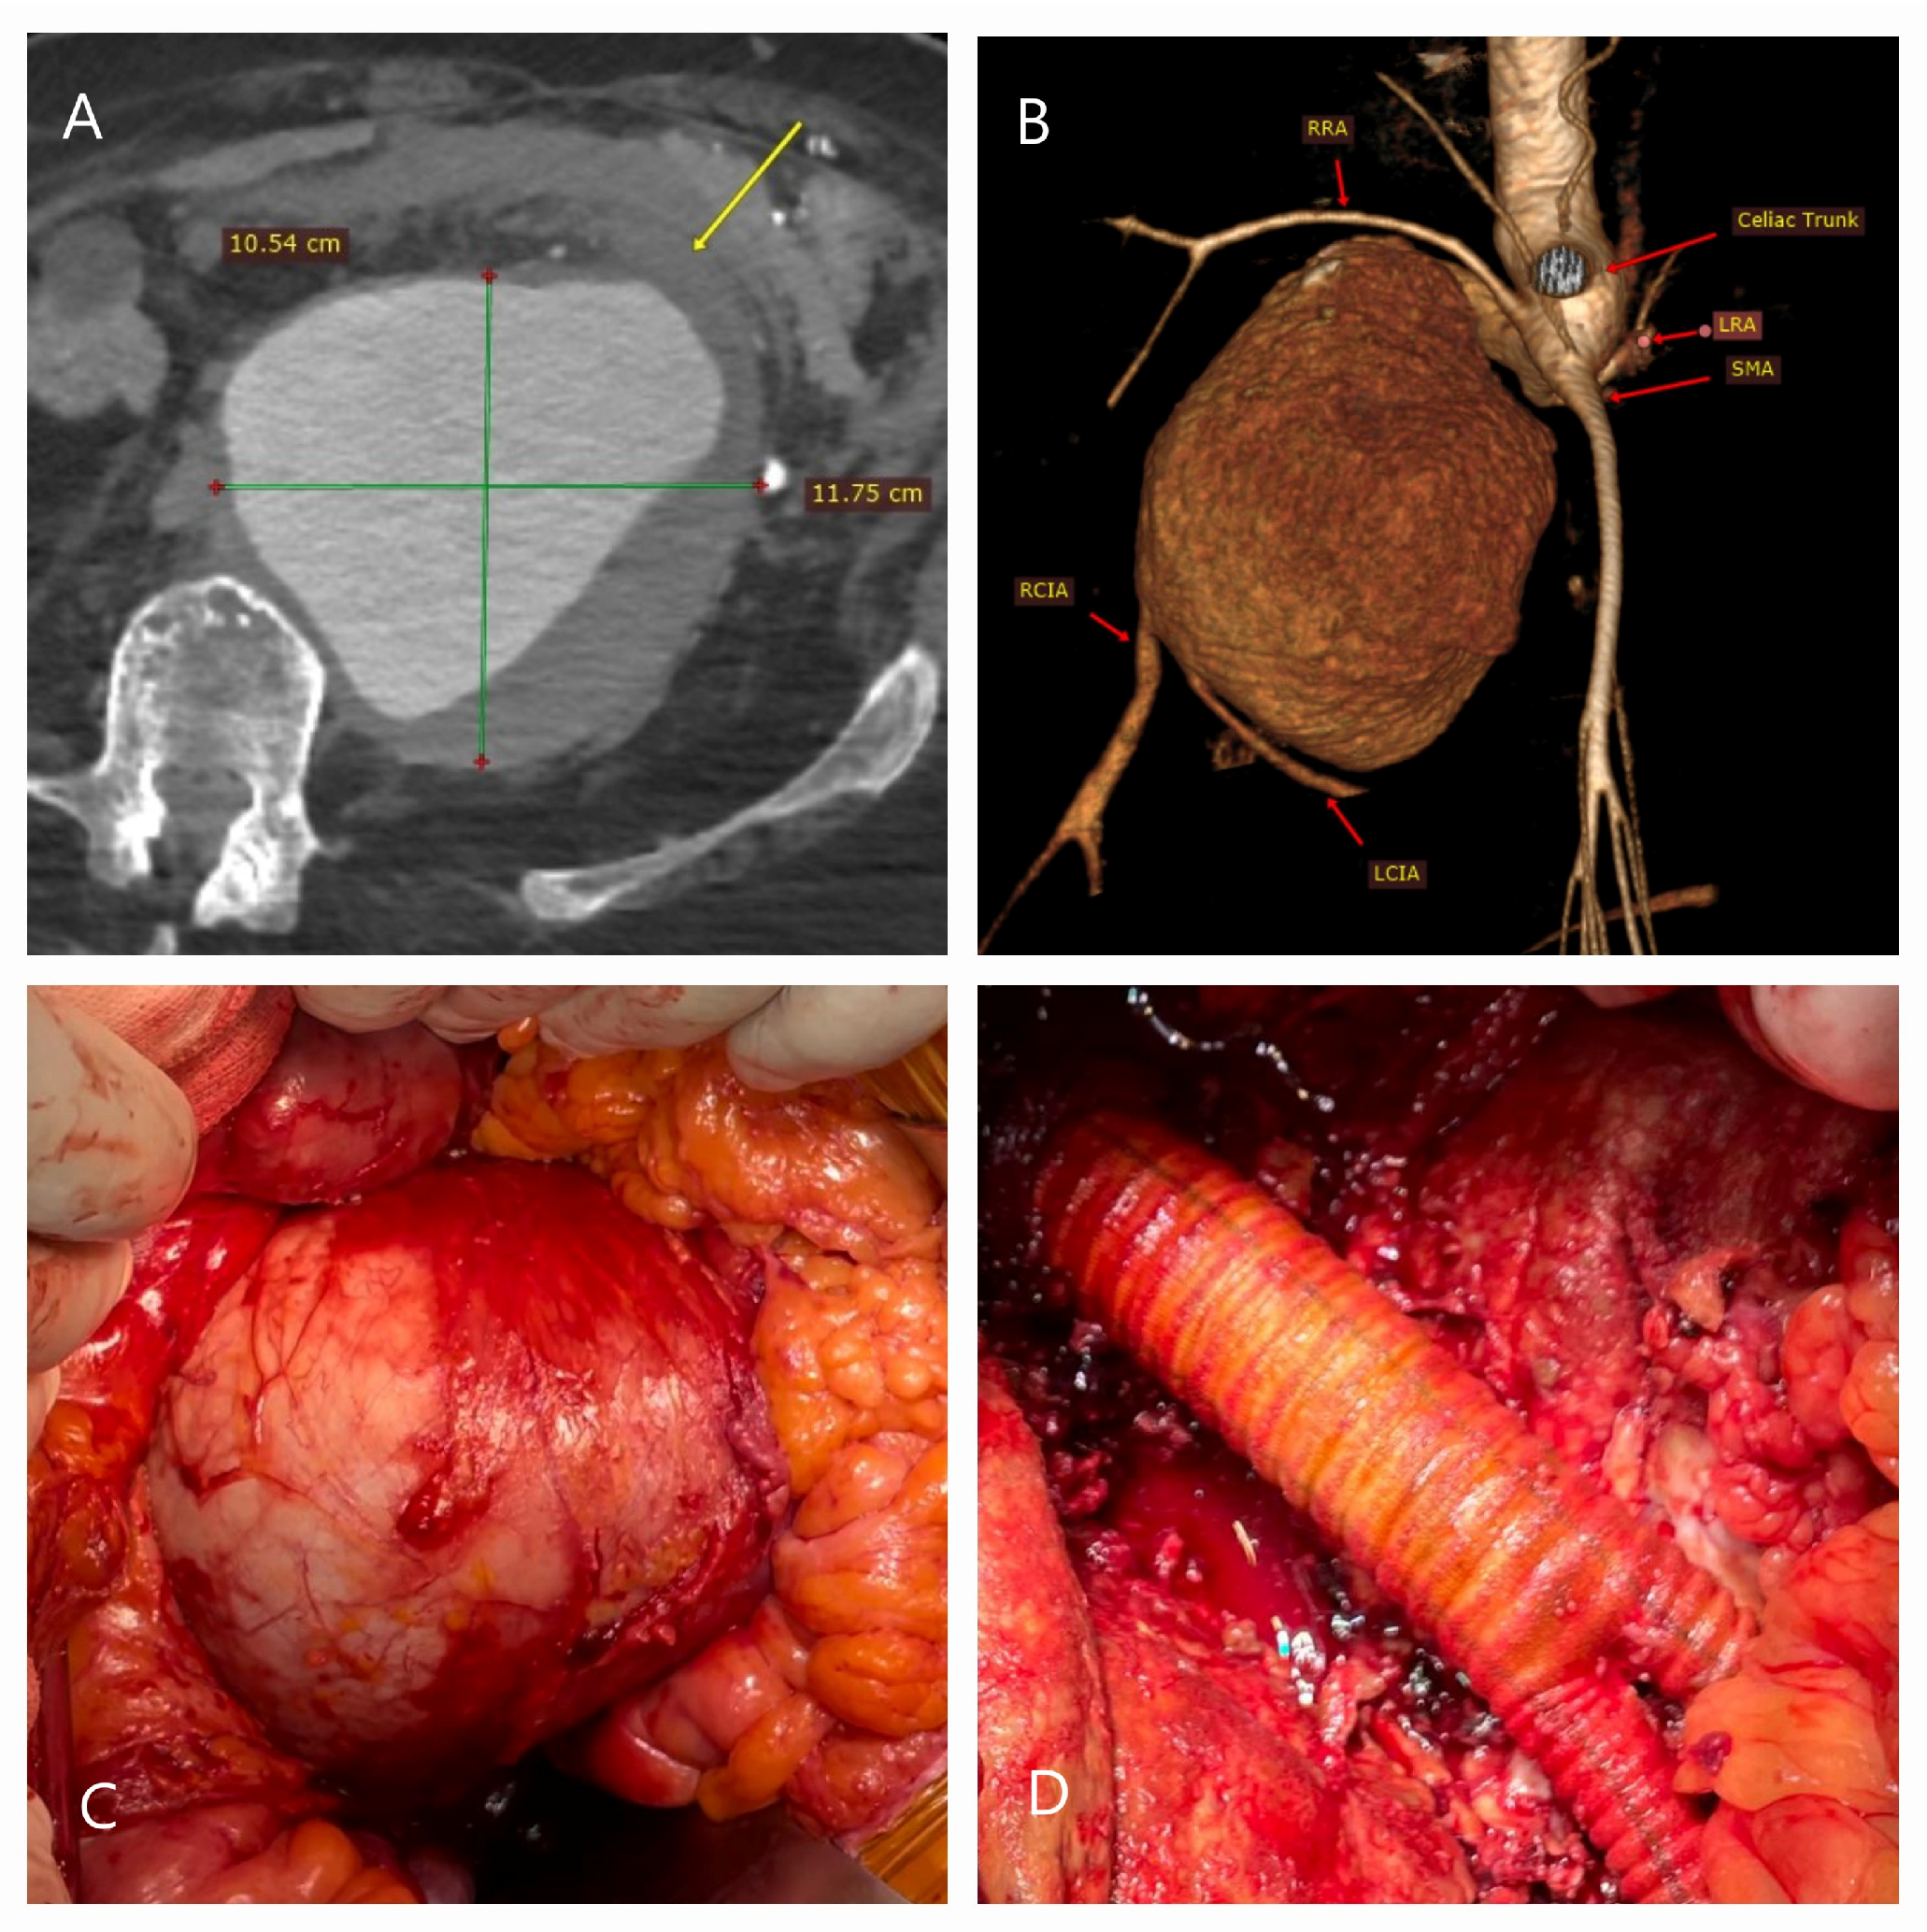

2.7. Open Surgical Repair Technique

5.1. Failure of EVAR

5.2. Conversion to Open Surgery